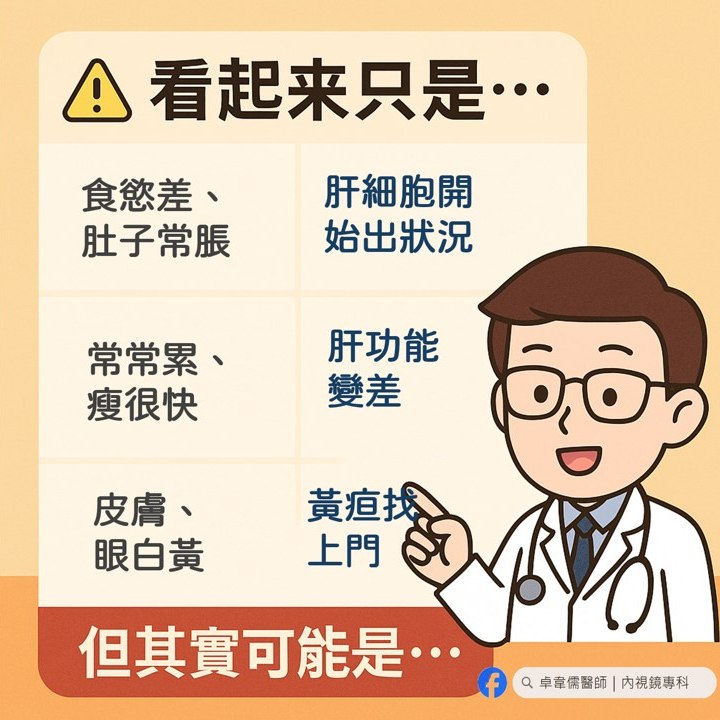

肝膽胃腸科醫師卓韋儒在粉專分享病例示警,一名40的男病患就診,原以為只是脹氣,拿點藥就好,但他見到對方「臉色不對、肚子大得不自然」,不僅皮膚灰暗呈土黃色、乾澀無光,眼白也偏黃,男子平躺後用手敲擊腹部還會聽見明顯聲響,翻身時也伴隨「水聲」。

卓韋儒醫師立刻驚覺不對勁,趕緊安排超音波檢查,影像出來後,在場所有人都瞬間安靜,因為男子根本不是脹氣,而是滿肚子的腹水,不僅有嚴重肝硬化,還有一顆11公分的巨大肝腫瘤。

卓韋儒醫師嚴肅提醒,「肝臟沒有痛覺,等到它把肚子撐到讓你覺得『脹』,往往都已經是晚期」,千萬別以為肚子大就是變胖,尤其是B、C肝帶原者,每半年的超音波追蹤檢查絕對不能省。